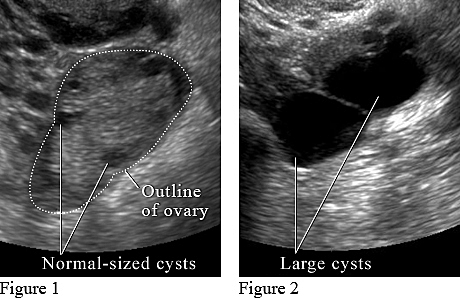

Used to detect Ovarian cancer by using high-frequency sound waves. Will check for ovarian cysts, tumors, fibroids, and polyps. A sonographer will most likely perform this test and will use a transducer. A radiologist will then interpret the results. Will take approx 30-60 minutes and will get results a couple of hours after the examination. Used for during an after pregnancy just in case.

Transvaginal Ultrasound Image

Showing a large cyst that could be cancerous. This is found in an ultrasound to detect Ovarian Cancer.